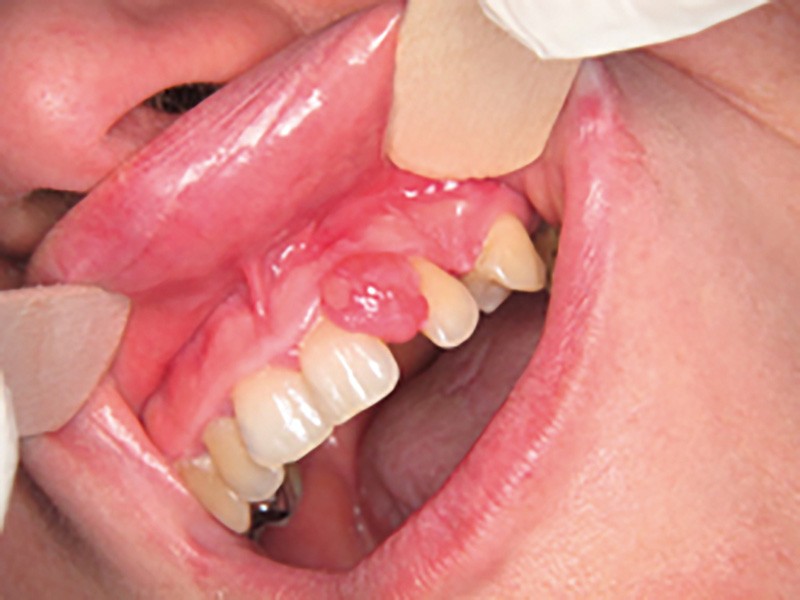

Motif de la consultation. Patiente de 25 ans venue consulter pour l’apparition d’une tuméfaction gingivale « disgracieuse » et non douloureuse.

Examen clinique. Il révélait une lésion nodulaire de 1 cm de grand axe, localisée entre 21 et 22 en malposition. Le nodule était érythémateux et ulcéré sur sa face vestibulaire. Il présentait un caractère sessile. Le sondage à hauteur de la 21 mettait en évidence une poche parodontale de 5 mm au niveau distal.

Synthèse. Le tableau clinique et l’examen anatomopathologique sont évocateurs d’une épulis fibroblastique ulcérée calcifiante et ossifiante. Cette forme se distingue des épulis inflammatoires et fibreuses par la présence d’une ulcération et d’une métaplasie calcifiante et osseuse. Le traitement repose sur l’exérèse et un suivi, car cette forme clinique est plus récidivante que les épulis fibreuses ou inflammatoires simples.